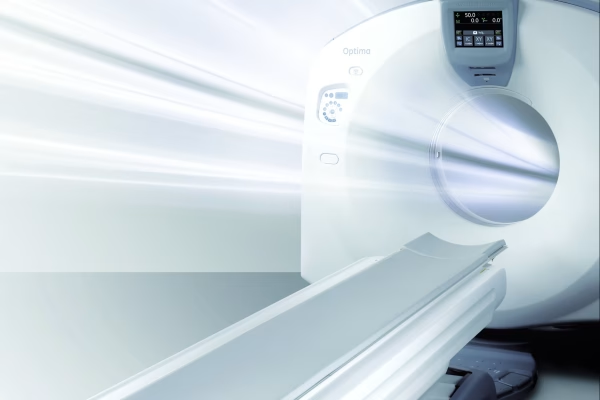

Scanner GE Optima CT520